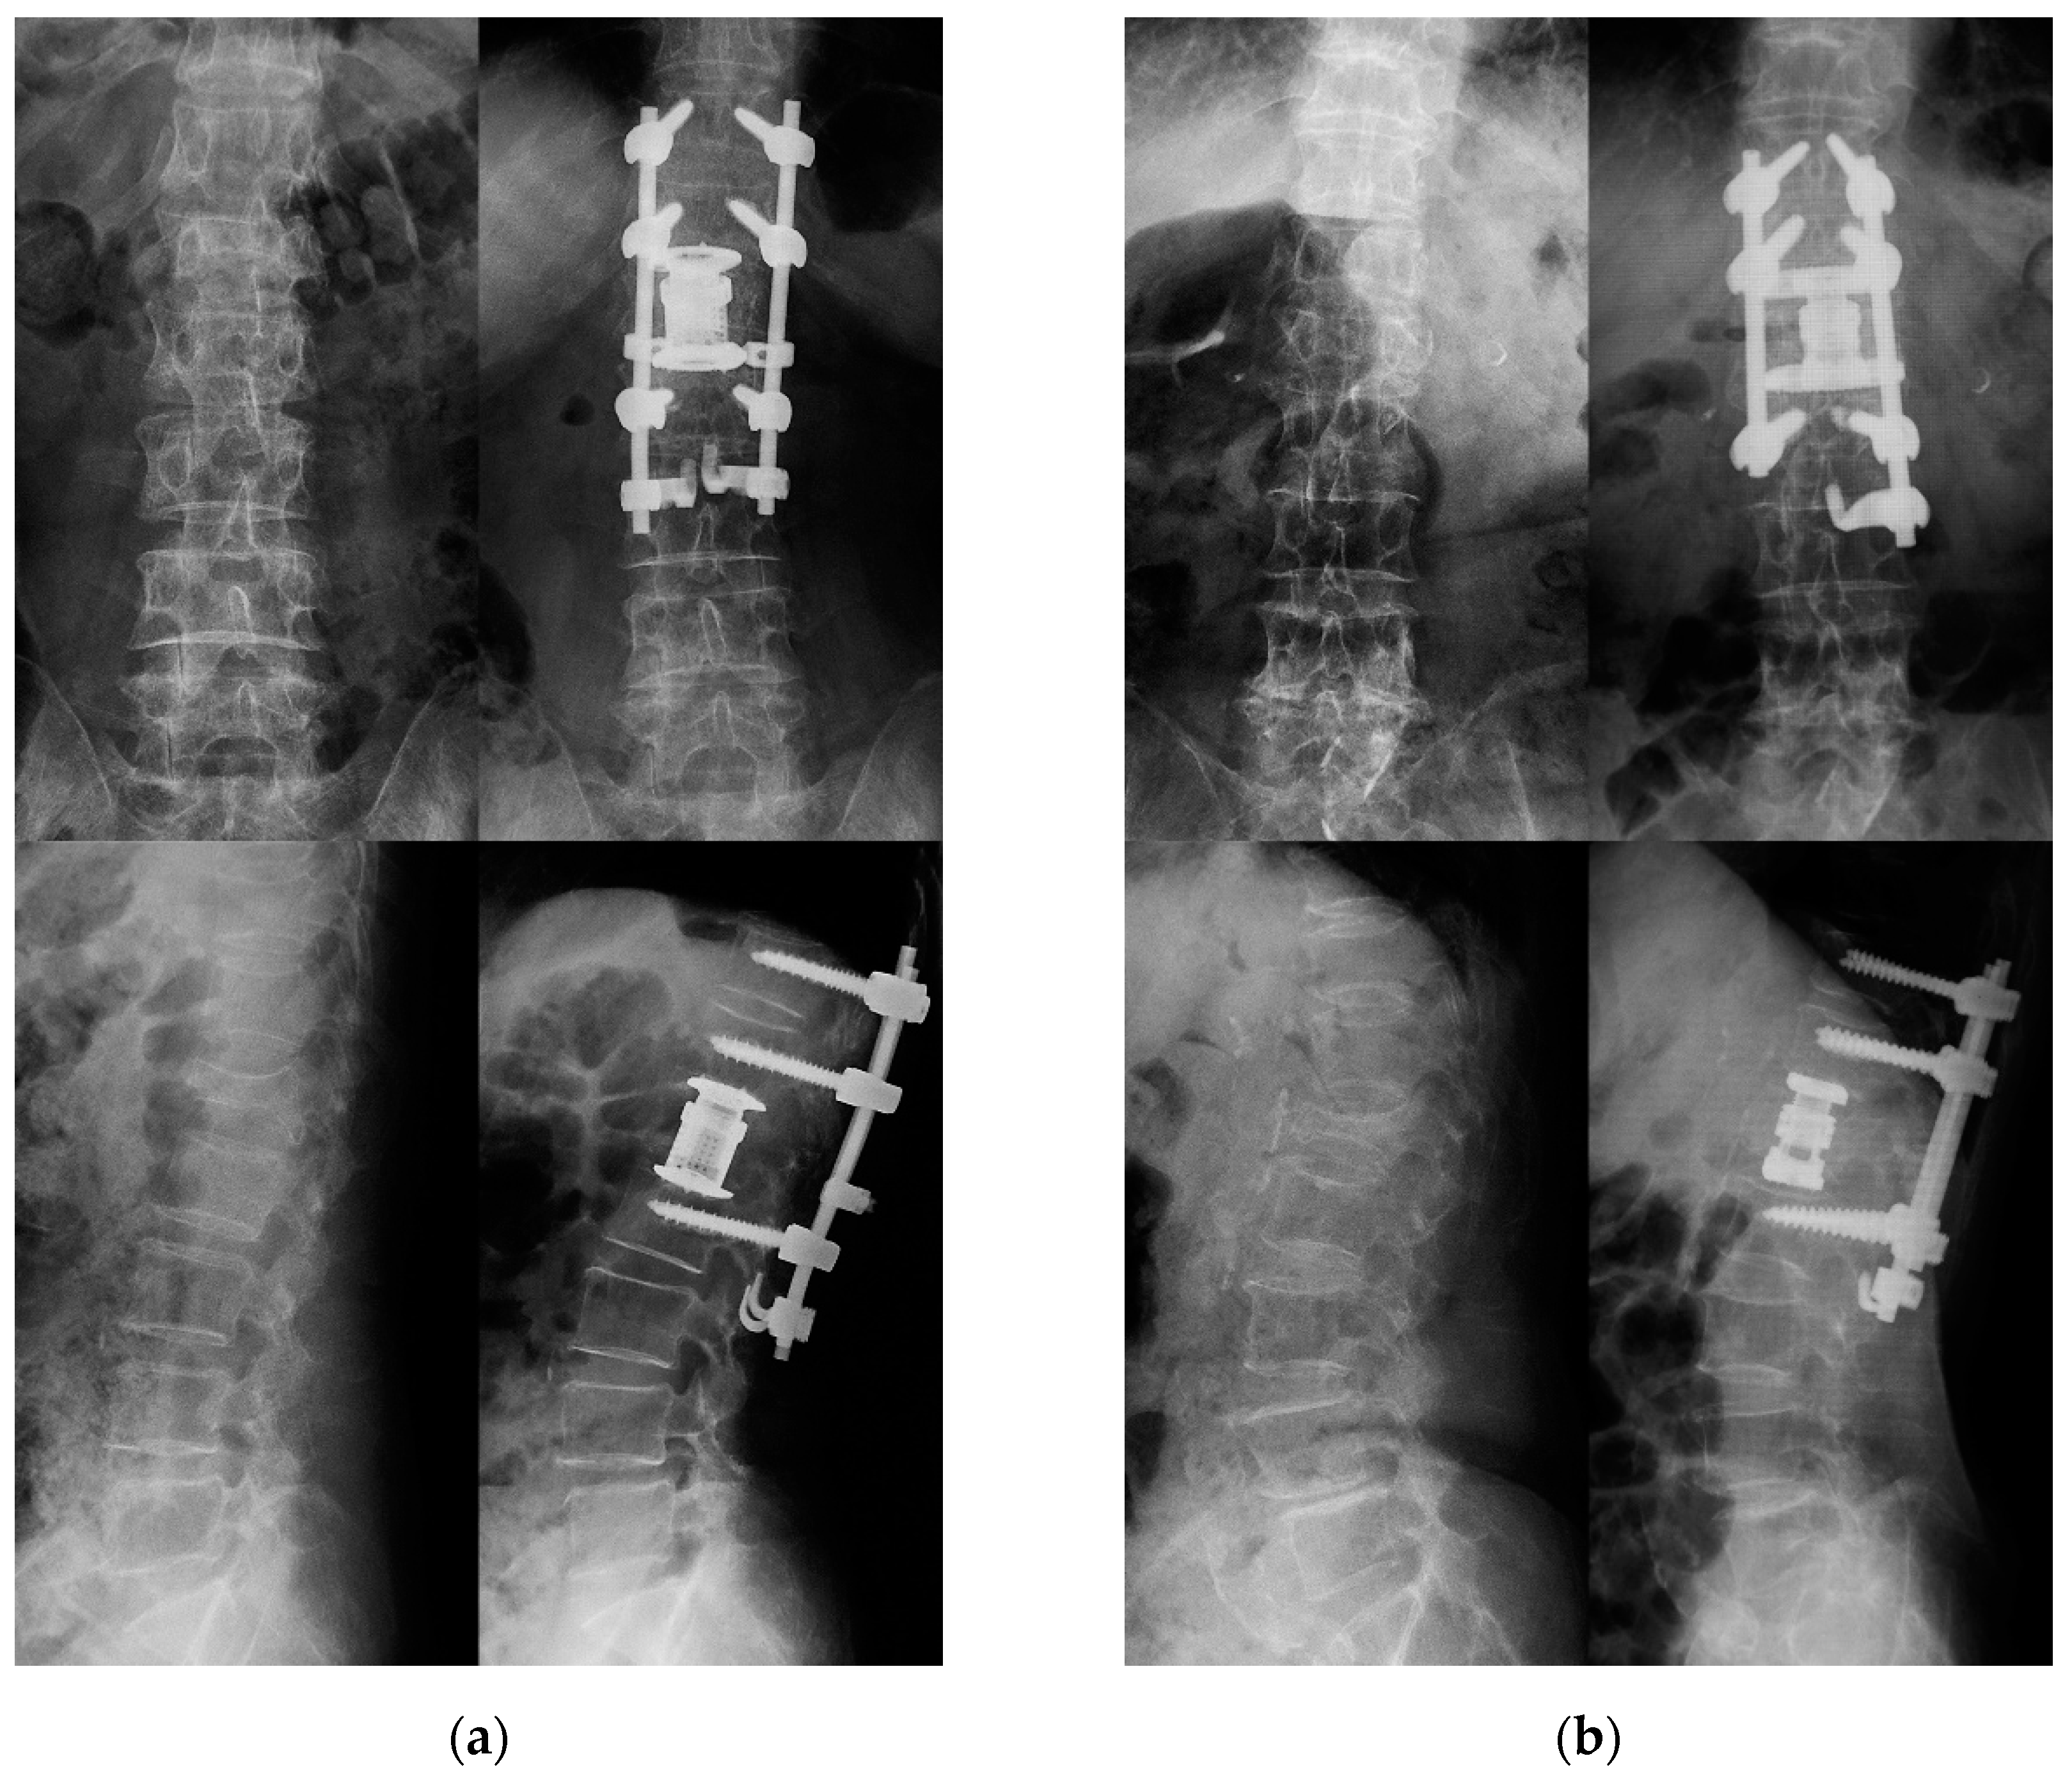

- Taiji, R.; Takami, M.; Yukawa, Y.; Hashizume, H.; Minamide, A.; Nakagawa, Y.; Nishi, H.; Iwasaki, H.; Tsutsui, S.; Okada, M.; et al. A Short-Segment Fusion Strategy Using a Wide-Foot-Plate Expandable Cage for Vertebral Pseudarthrosis after an Osteoporotic Vertebral Fracture. J. Neurosurg. Spine 2020, 33, 862–869. [Google Scholar] [CrossRef]

- Nakashima, H.; Kanemura, T.; Satake, K.; Ito, K.; Tanaka, S.; Segi, N.; Ouchida, J.; Ando, K.; Kobayashi, K.; Ishiguro, N.; et al. Lateral Approach Corpectomy and Reconstruction after Anterior Longitudinal Ligament Release in Cases with Fixed Kyphosis: A Technical Note and a Preliminary Case Series. J. Clin. Neurosci. 2020, 78, 164–169. [Google Scholar] [CrossRef] [PubMed]